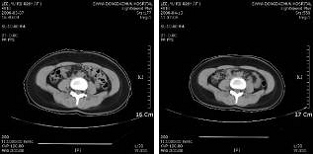

½Ã¼ú ÀüÈÄ CTÃÔ¿µÀ¸·Î ÇÇÇÏÁö¹æÃþÀÇ º¯È­¸¦ °üÂûÇÑ ¸ð½À. ½Ã¼ú Àü ÇÇÇÏÁö¹æÃþÀÇ ´Ü¸éÀûÀÌ 224.09§²¿¡¼­ 200.92§²·Î ÁÙ¾îµé¾ú´Ù.